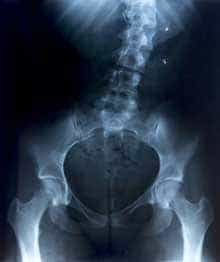

X線 腰椎の歪み